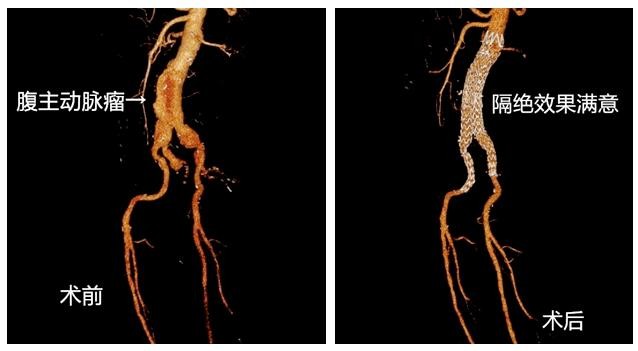

腹主动脉瘤

手术展示